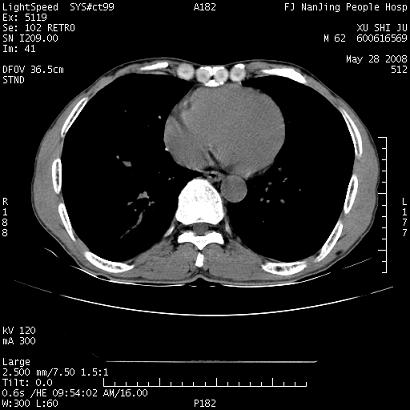

以下是引用qiushi在2008-5-28 20:01:00的发言:[br]空洞周围环状磨玻璃影(日晕征),考虑肺曲霉菌病.

以下是引用clj20在2008-5-28 20:50:00的发言:[br]鉴别诊断:癌性空洞壁结节。建议变换体位ct透视.[br][br]

以下是引用yuhongjun在2008-5-29 4:28:00的发言:[br]空洞周围环状磨玻璃影(日晕征),考虑肺曲霉菌病。支持! [br] [br]

以下是引用lrj在2008-5-28 21:10:00的发言:[br]所示应该是正常结构,是对称的,多个层面都有!也不像是内乳动脉或是肿大淋巴结![br]右下肺渗出性病变伴空洞形成,其洞内见一结节,以下诊断都有可能:1 右下肺曲菌感染, 2右下肺结核空洞形成伴曲菌感染!3右下肺结核空洞伴壁内占位形成,虽说后者发生的几率很低 但作为我们应该多考虑一下吧!最重要的结合临床